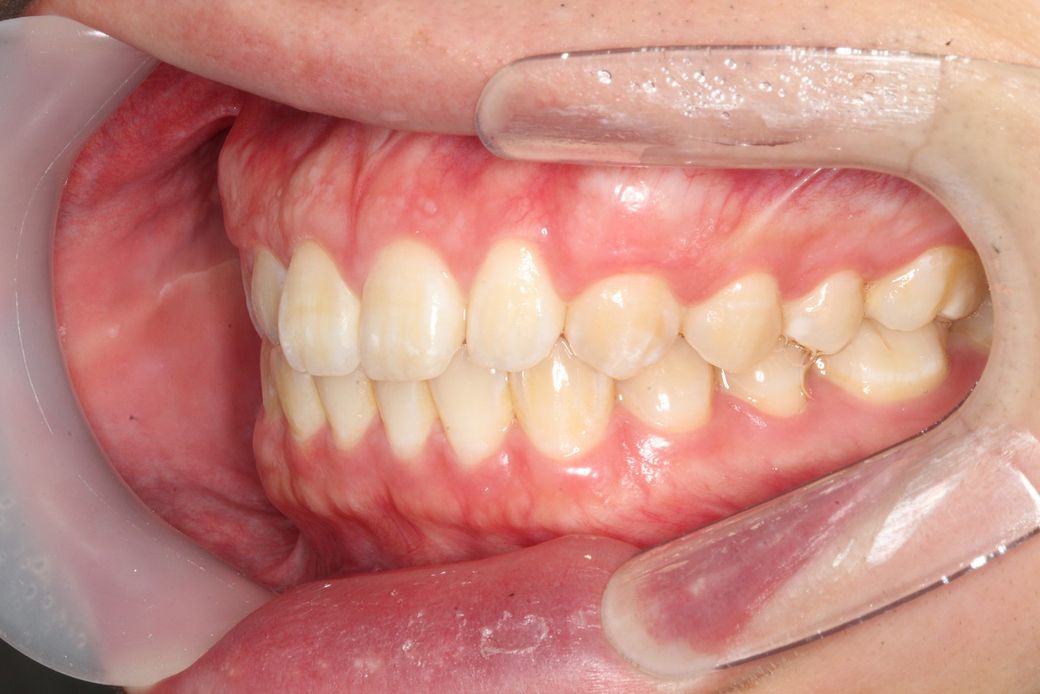

치아 앞니쪽에 반대교합이 있어서 분분교정할 생각인데 부분교정으로 치료가능해 보일까요?

앞니빼고 나머지는 괜찮아 보일까요?

윗니가 아랫니를 덮는 양또는 윗니가 앞으로 나온양이조금 적다고는 하는데 골격적 문제라 어쩔 수 없다는데 맞나요?

부분 교정으로도 어려워 보이며 전체 교정도 현재 증상을 개선하기가 쉽지 않아 보입니다. 워낙 다른 부위에 치열 상태는 나쁘지 않기 때문에 교정을 하더라도 현재 증상에 대한 개선이 어려울 수도 있어 보입니다. 또한 치열 배열 뿐만 아니라 골격적 문제가 동반되고 있어 골격적인 부분은 교정으로 수정할 수가 없습니다.

지금 정도의 골격적 부조화는 일반인들은 알아차리지 못하며 양악 등을 수술을 권하는 정도도 아닙니다.

사진상으로 보면 크게 문제가 있어보이지는 않습니다. 하지만, 기능상으로 문제가 있다면 교정을 하시거나 심미적개선을 원하신다면 교정을 하시면될것같아요.